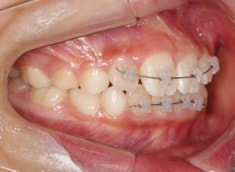

治療法:拡大プレート+フルパッシブブラケット(クリアスナップ)

治療後(8ヶ月後)

治療中